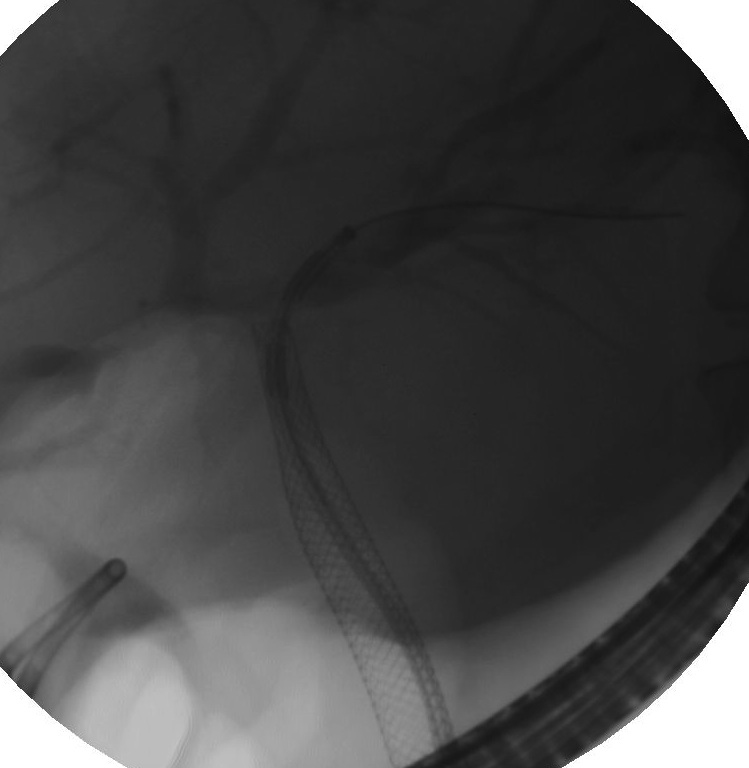

B5_img.jpg

Radiofrequency ablation is used to treat some bile duct cancers

• Radiofrequency ablation, which uses high-energy radio waves to treat inoperable bile duct cancers and reduce pain and other symptoms.